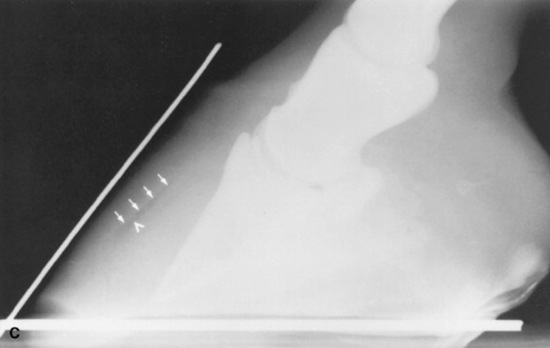

Radiographic examinations should be performed on the affected digits of horses suspected to be developing laminitis. The initial examinations should include lateromedial and 65-degree dorsoproximal-palmarodistal projections. These views should be taken to assess the appearance of the distal phalanx, the soft tissues of the hoof wall and corium, and their relationship. Lateromedial examinations are periodically repeated to check the progression of the disease. Radiographic signs of laminitis include ventral displacement of the extensor process with respect to the coronary groove of the hoof wall, increased distance between the dorsal cortex of the distal phalanx and the surface of the hoof wall, and ventral rotation of the tip of the distal phalanx. Linear radiolucencies are noted interior to the hoof wall in cases where the corium has separated from the epidermal laminae. Increasing degrees of rotation of the distal phalanx and increases in the distance between the dorsal surface of the distal phalanx and the hoof wall indicate progression of the disease (Fig. 38-30).

Fig. 38-30 A, Lateromedial radiograph of a normal digit. Two radiopaque markers can be seen. One has been placed on the block below the foot to mark the bearing surface of the wall, and the other marker identifies the location of the dorsal surface of the hoof wall. Notice that the dorsal surface of the hoof wall and the dorsal cortex of the distal phalanx are parallel, and that the distance between them, the soft tissue thickness (T), is approximately 25% of the distance from the tip of the distal phalanx to the articulation of the distal phalanx and the navicular bone, that is, the length of the distal phalanx (L). B, Lateromedial radiograph of a digit from a horse with severe laminitis. The distal phalanx has dropped ventrally without rotating. This phenomenon is seen in some horses with laminitis. The most consistent radiographic manifestation in such cases is an increased distance between the dorsal cortex of the distal phalanx and the dorsal surface of the hoof wall. The soft tissue thickness, as measured between the dorsal cortex and the dorsal surface of the hoof wall, in this case is 45% the length of the distal phalanx. The soft tissue thickness is normally less than 28% of the distal phalanx length for thoroughbred racehorses. C, Lateromedial radiograph of a digit from a horse with severe laminitis. Note the linear radiolucency dorsal to the distal phalanx (arrowhead). This lucency indicates a separation between the corium and primary epidermal laminae and marks the inner aspect of the hoof wall (arrows). The dorsal cortex of the distal phalanx is rotated approximately 14 degrees with respect to the inner surface of the hoof wall. Note that the dorsal and inner surfaces of the hoof wall are not parallel. This is the result of rasping along the distal portion of the dorsal surface of the hoof wall. The soft tissue thickness in this case is greatly increased to almost 42% of the distal phalanx length.

One of the earliest and most reliable radiographic signs of laminar deformity is an increase in distance between the dorsal surface of the hoof wall and the dorsal cortex of the distal phalanx. When the laminar suspending mechanism fails, weight-bearing forces cause the distal phalanx to displace distally or rotate away from the dorsal hoof wall, and the increased distance between the structures can be quantitated radiographically. Increased distance between the dorsal hoof surface and the dorsal cortex of the distal phalanx was significantly associated with increased laminar deformity during laminitis.221

A laminar index measurement has been developed to reduce the need to account for differences in radiographic magnification when comparing radiographs from different hospitals, from different breeds, or from different sizes of horses. It is useful to calculate the laminar index adjacent to the proximal and distal aspects of the dorsal cortex of the distal phalanx. The proximal laminar measurement is taken as the shortest distance between the linear portion of the dorsal cortex of the distal phalanx and the dorsal surface of the hoof wall immediately distal to the extensor process of the distal phalanx; the distal laminar measurement is taken in the same way, 5 to 6 mm proximal to the tip of the distal phalanx (see Fig. 38-30). The proximal and distal measurements are used to produce proximal and distal laminar indices by expressing them as a proportion of the length of the palmar cortex of the distal phalanx, as measured from the tip of the distal phalanx to its articulation with the navicular bone. The palmar cortex measurement serves as an index of foot size, and if the proximal or distal measurements spanning the laminae are increased in relation to the length of the palmar cortex, laminar deformity has occurred. Both the proximal and the distal laminar index measurements should be less than 30% of the palmar cortex length. The index measurements ranged between 20% and 28% for nonlame racing thoroughbreds221,233 and were greater than 30% in horses with laminitis,234 ranging up to 50% to 55% in those with severe laminar deformity.221 If the proximal and distal laminar indices are almost equal and both are greater than 30%, the distal phalanx has sunk in relation to the hoof capsule, without rotation (see Fig. 38-30). When both indices are greater than 30% and the distal index is greater than the proximal index, sinking and rotation of the distal phalanx have both occurred. Sinking generally indicates that laminar degeneration involves more than the dorsal wall laminae and carries a worse prognosis than for horses with rotation alone.